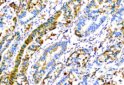

IHC-double stain

Immunohistochemical double staining 染色標的:FoxP3 IL1RN